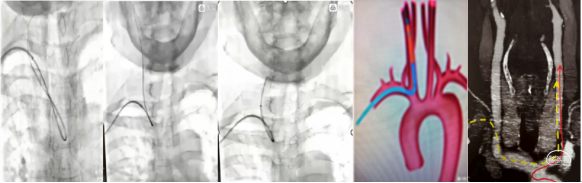

3)5F-140cm sim2导管能够顺利超选右侧颈总动脉,7F赛诺远端通路导引导管推送很顺利到达颈內动脉C2-C3段建立通路。

4)、7F赛诺远端通路导引导管0.079in内腔,能够兼容所有5F中间导管到达大脑中动脉M1段。

成袢后回拉sim导管超选颈总动脉,旋转sim导管解袢呈“勾型”,将泥鳅导丝走行颈内动脉起到支撑作用,同轴输送Nueron MAX 长鞘到达颈内动脉远端建立稳定的血管通路,撤出长sim导管,泥鳅导丝或微导丝、微导管导引下沿Nueron MAX 长鞘将中间导管顺利输送至病变目标血管进行抽吸取栓或支架取栓。下图1-4所示。

牛型主动脉弓超选:泥鳅导丝携带125cm单弯造影导管或猪尾巴造影导管半伸直状态下将泥鳅导丝进入左侧颈总动脉远端,同轴输送Nueron MAX 长鞘到达颈内动脉远端建立通路,微导丝、微导管导引下沿Nueron MAX 长鞘将中间导管顺利输送至病变目标血管进行抽吸取栓或支架取栓,下图5所示。